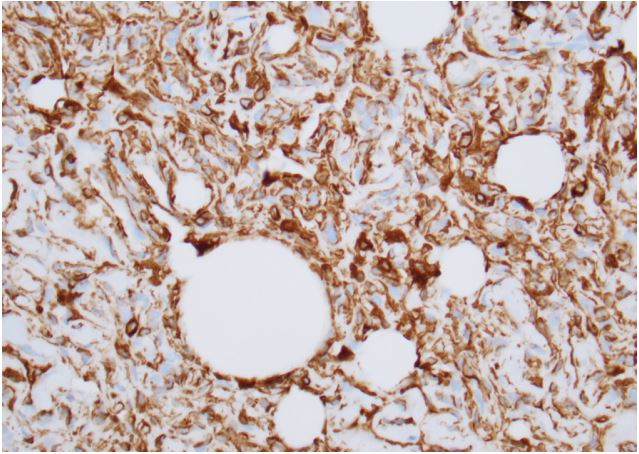

We present a case of a 32-year-old male who presented to the hospital after a motor vehicle accident resulting in multiple facial bone fractures, displaced right third and fourth lateral rib fractures, right lung contusion, right apical pneumothorax, and hemothorax (Figure 1). The patient underwent multiple surgeries, which included right 4th rib open reduction and internal fixation (ORIF), VATS with right upper lobe wedge resection, mechanical pleurodesis, and chest tube placement. Surgical pathology of the VATS specimen revealed a 2 mm irregular nodule with morphologic and immunohistochemical features favoring a meningothelial nodule (Figures 2 and 3). The immunohistochemical stain was positive for vimentin (Figure 4) and epithelial membrane antigen (EMA) and negative for CD56, progesterone receptor, and cytokeratin. A diagnosis of benign pulmonary meningioma was made. The lesion appeared to be excised entirely on the biopsy specimen. Interestingly, this lung nodule was not visualized on any prior chest X-ray or computed tomography (CT) of the chest and was first noted only on the pathology specimen. CT of the head (Figure 5) and the entire spine did not show any primary brain or spinal meningioma, enabling the diagnosis of primary pulmonary meningioma.

Figure 4: Immunohistochemical examination showing tumor cells stained positive for vimentin.